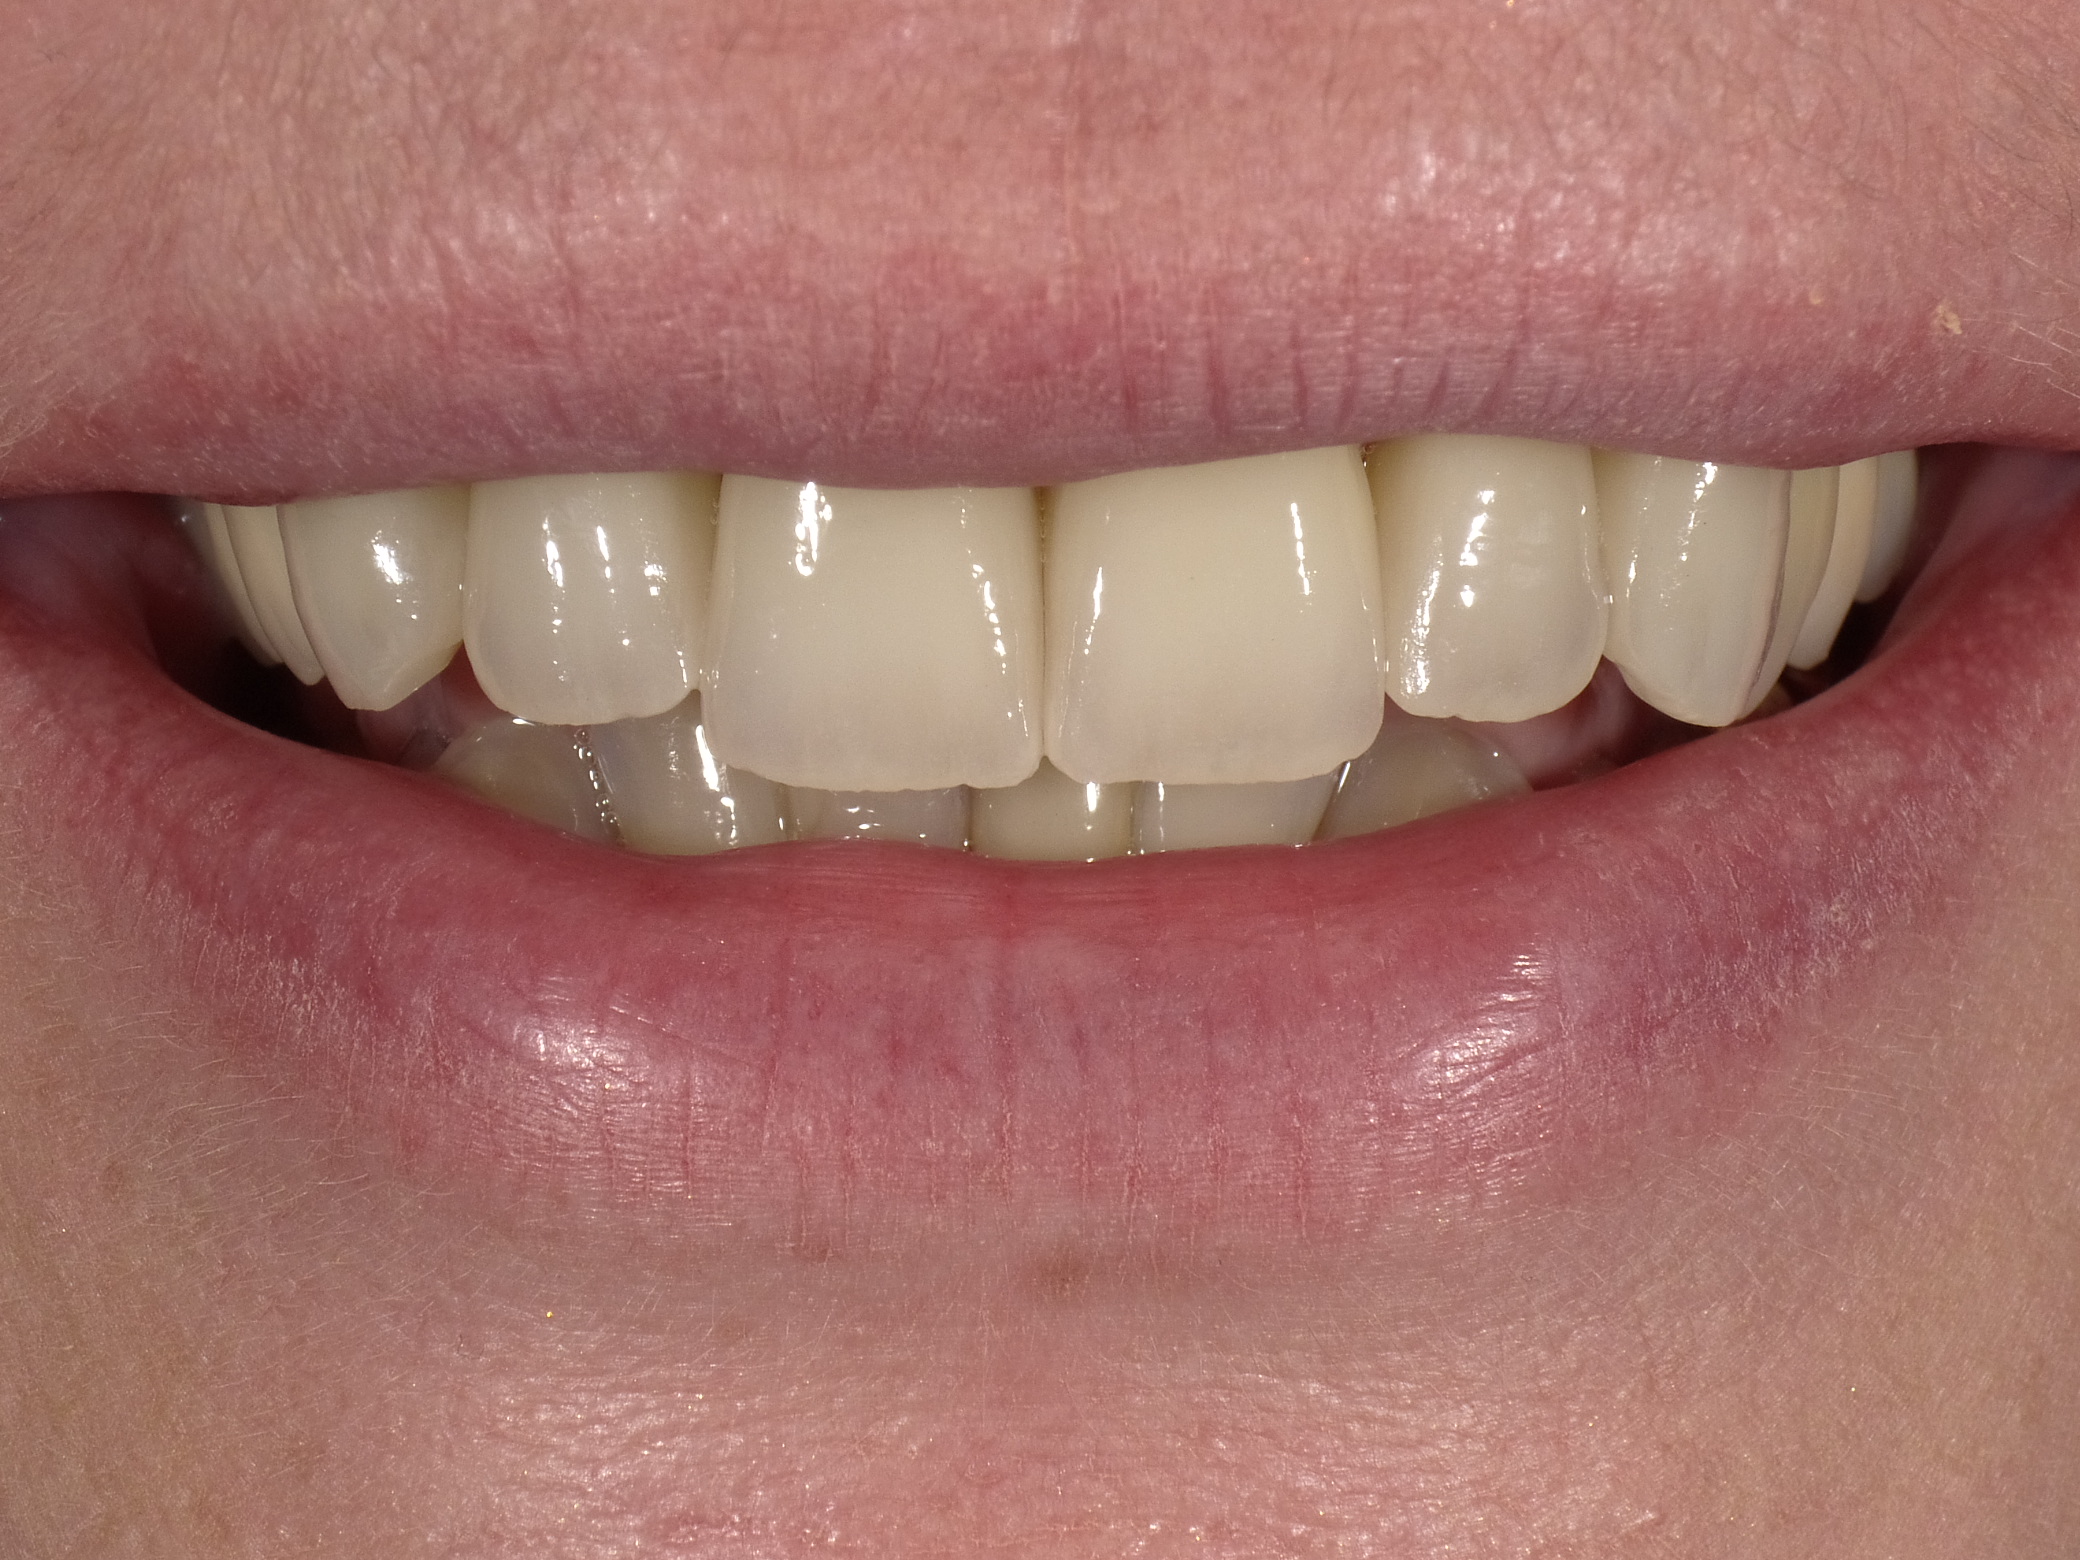

Diverse Vorbehandlungen mit für die Patientin absolut inakzeptablem Ergebnis

Vorher: Diverse Vorbehandlungen mit für die Patientin absolut inakzeptablem Ergebnis

Komplette Veränderung mit vollkeramischen Kronen und Veneers in nur 2 Langzeitterminen; auch hier nachher ganz anderes Auftreten der Patientin, die ihre Zähne jetzt gerne zeigt und wieder gerne lacht

Nachher: Komplette Veränderung mit vollkeramischen Kronen und Veneers in nur 2 Langzeitterminen; auch hier nachher ganz anderes Auftreten der Patientin, die ihre Zähne jetzt gerne zeigt und wieder gerne lacht